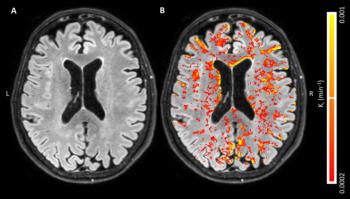

Figure 1. A, Axial fluid-attenuated inversion recovery image in a 68-year-old man with, B, corresponding blood-brain barrier leakage rate (Ki) maps superimposed. Leakage rate values appear diffusely distributed on both images, with some periventricular hot spots. Leakage manifests in normal-appearing white matter, white matter hyperintensities and gray matter. Voxels with low signal-to-noise ratio in MRI signal intensity were removed, and leakage rate map was masked to cerebrum.